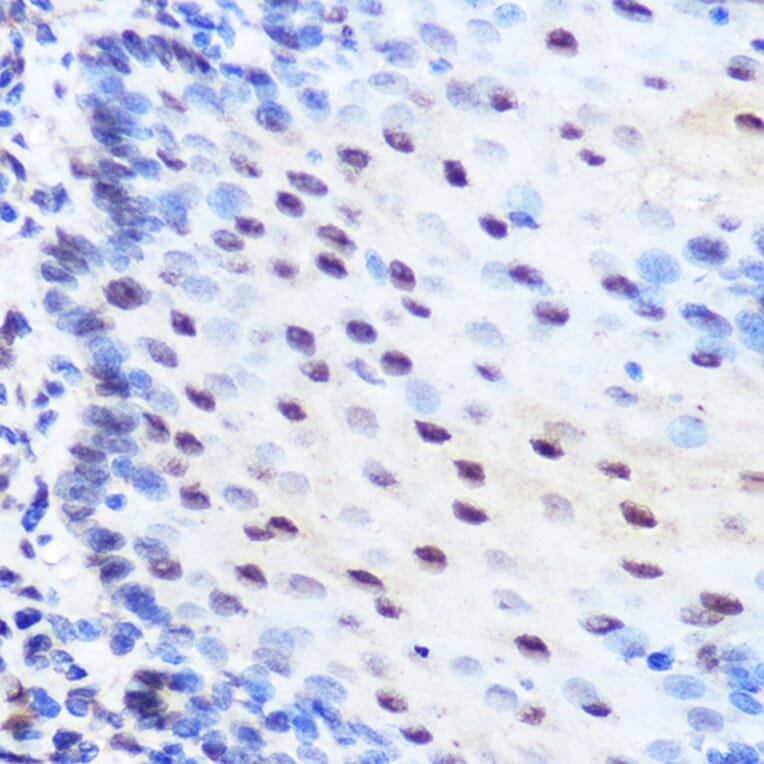

Immunohistochemistry analysis of paraffin-embedded rat brain using Anti-ZNF207/BUGZ Antibody (A307387) at a dilution of 1:100 (40x lens). Perform microwave antigen retrieval with 10 mM Tris/EDTA buffer pH 9.0 before commencing with IHC staining protocol.

Immunohistochemistry analysis of paraffin-embedded human esophageal using Anti-ZNF207/BUGZ Antibody (A307387) at a dilution of 1:100 (40x lens). Perform microwave antigen retrieval with 10 mM Tris/EDTA buffer pH 9.0 before commencing with IHC staining protocol.

Immunohistochemistry analysis of paraffin-embedded mouse spinal cord using Anti-ZNF207/BUGZ Antibody (A307387) at a dilution of 1:100 (40x lens). Perform microwave antigen retrieval with 10 mM Tris/EDTA buffer pH 9.0 before commencing with IHC staining protocol.